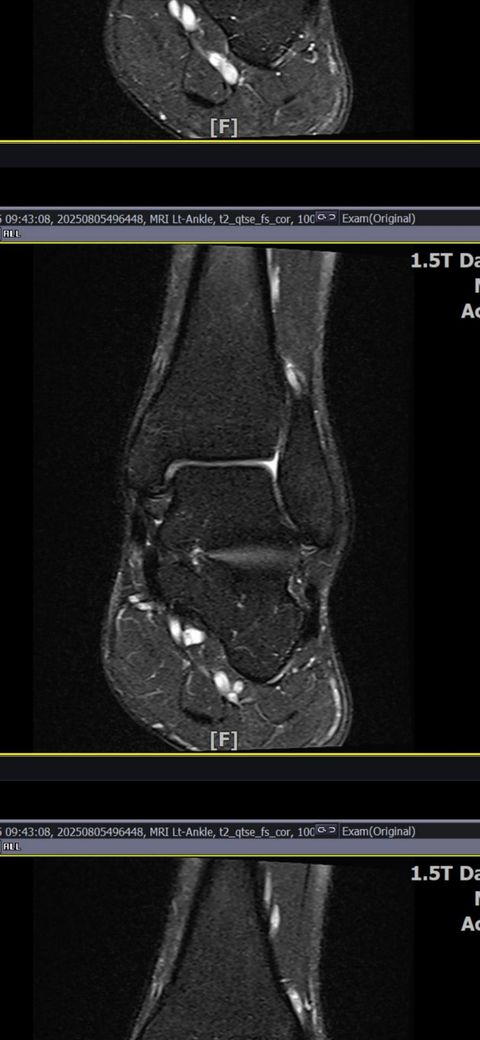

발목인대 상태 질문드립니다. (mri사진 첨부)

그런데 다친 지 2주 뒤부터 발목이 쑤시듯 아파 병원에서 초음파 검사를 했고, 전거비인대(ATFL) 2도 염좌 진단을 받았습니다. 이후 약 6주 동안 주 1회씩 충격파, 물리치료, 도수치료 등을 받았습니다. (고정치료는 시기가 늦었다며 진행하지 않았습니다.)

그래도 통증이 남아 8월 5일에 MRI를 촬영했는데, 병원에서는 “인대는 이어져 있고, 이 정도면 재활운동으로 호전될 것”이라는 설명을 들었습니다.

하지만 현재 9월, 다친 지 3개월이 다 되어가는데도 활동(걷기, 뛰기) 시 여전히 쑤시는 통증과 미열감 같은 불편감이 남아 있어 걱정됩니다.

MRI 상 전거비인대와 발목 상태가 정말 회복 단계인지, 아니면 만성으로 넘어가는 건 아닌지 전문가분들의

의견을 듣고 싶습니다.

• 4번 째 사진

올려주신 mri를 보면 전거비인대는 연속성이 유지되고 있고 파열이나 큰 손상 흔적은 없어 재활로 회복 가능한 상태로 보입니다 다만 3개월 가까이 활동 시 통증과 미열감이 남아 있는 것은 조직 회복이 아직 완전히 끝나지 않았거나 주변 연부조직 관절 움직임 제한 등으로 인한 과민 반응일 수 있습니다.

초음파와 비교하면 mri 상으로 인대 연속성이 확인되므로 심각한 악화나 재파열은 아닌 것으로 판단됩니다

MRI상에서는 인대의 회복이 이루어지고 있는 덧으로 보이지만 인대의 회복은 소요되는 시간이 오래 걸리고, 주변 근육의 약화나 기능 저하로 인해 통증이나 불편감이 지속될 수 있습니다.